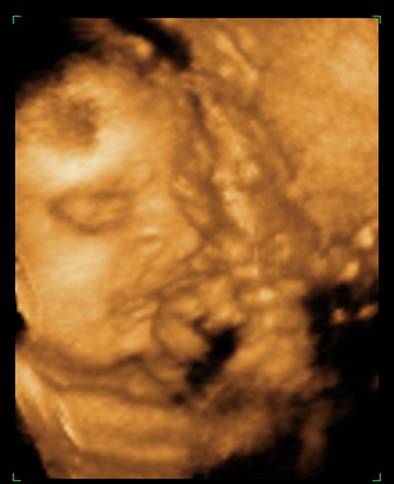

Voltunk 4D-n, rakok fel képeket mindjárt. (apja oda sem nézett, amikor mutatták az arcocskáját, csak nyavajgott, hogy mikor van már vége, érdemes volt elvinni...) De egyre kisebbnek mérik ezt a babát, és kezdek aggódni. Inkább 29 hetes méretei vannak, mint 30... És a súlya még mindig csak 1366, közben itt már mindenkinek minimum másfél kiló fölötti... :cry:

na, még ezeket megmutatom a kis pöttömről:

Kép

Boruska Fel a fejjel! Aludj egy jót! Embered biztos csak nyűgös volt, majd holnap biztos örömmel nézegeti édes kismanótokat a képeken. És miként sok okos már írta, a méretek csak átlagok, s ezek ugye a nagyobbakból és a kisebbekből tevődnek össze. Könnyebb megszülni egy 3 kg-os babát, mint egy 4,5 kg-t :) . És 1 hetes méret eltérés igazán semmitmondó. Valamint a súlybecslés az egyik legbizonytalanabb tényező, szóval ezen tényleg ne aggódj! Az utolsó képen én úgy látom mosolyog Berci. Álmodj ezzel a kis mosollyal!